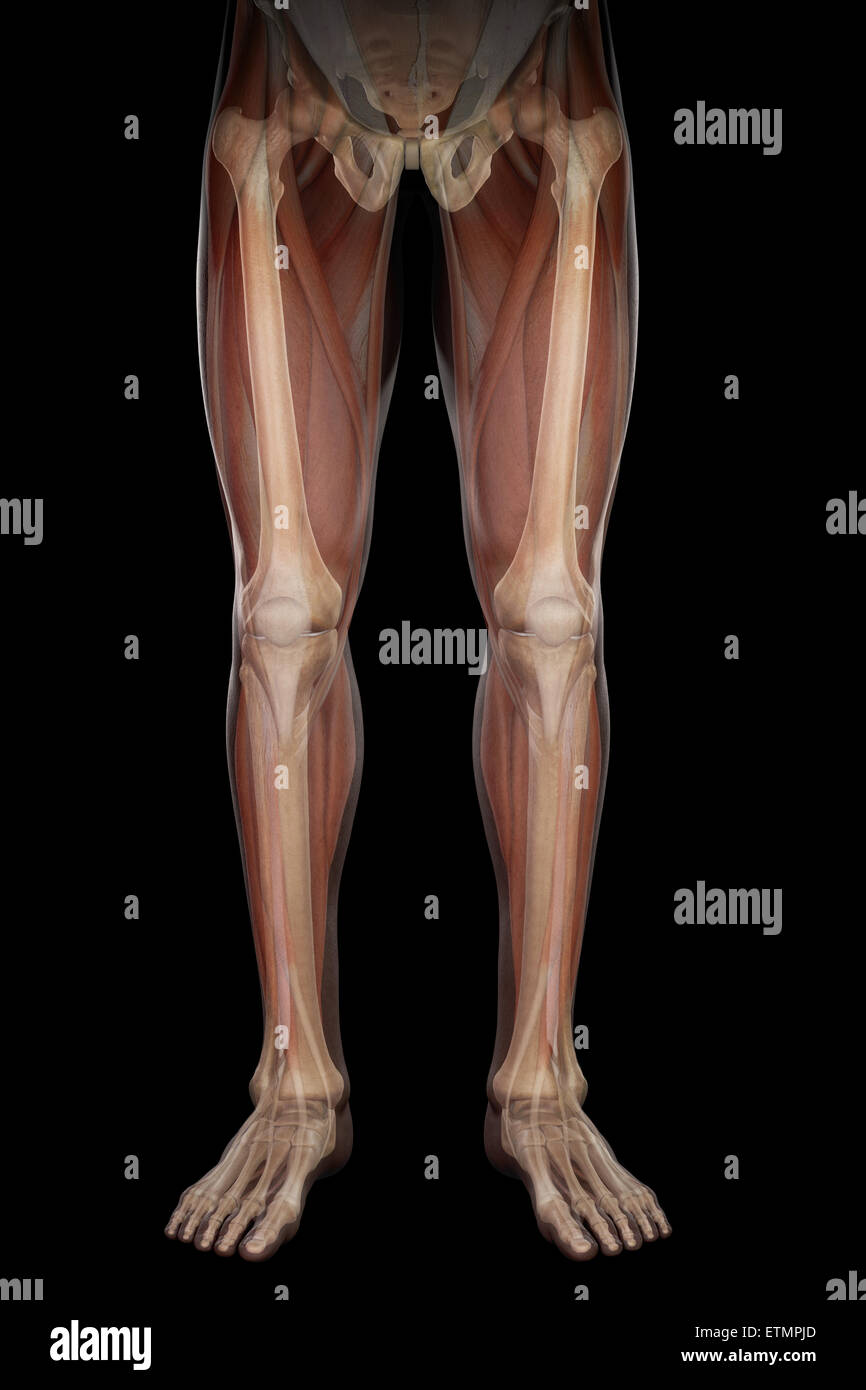

Illustration of the musculature and skeletal structure of the lower legs, visible through skin. Stock Photohttps://www.alamy.com/image-license-details/?v=1https://www.alamy.com/stock-photo-illustration-of-the-musculature-and-skeletal-structure-of-the-lower-84049343.html

Illustration of the musculature and skeletal structure of the lower legs, visible through skin. Stock Photohttps://www.alamy.com/image-license-details/?v=1https://www.alamy.com/stock-photo-illustration-of-the-musculature-and-skeletal-structure-of-the-lower-84049343.htmlRMETMNP7–Illustration of the musculature and skeletal structure of the lower legs, visible through skin.

Illustration of the musculature and skeletal structure of the legs, visible through skin. Stock Photohttps://www.alamy.com/image-license-details/?v=1https://www.alamy.com/stock-photo-illustration-of-the-musculature-and-skeletal-structure-of-the-legs-84048427.html

Illustration of the musculature and skeletal structure of the legs, visible through skin. Stock Photohttps://www.alamy.com/image-license-details/?v=1https://www.alamy.com/stock-photo-illustration-of-the-musculature-and-skeletal-structure-of-the-legs-84048427.htmlRMETMMHF–Illustration of the musculature and skeletal structure of the legs, visible through skin.

Illustration showing the musculature and skeletal structure of the legs, visible through skin. Stock Photohttps://www.alamy.com/image-license-details/?v=1https://www.alamy.com/stock-photo-illustration-showing-the-musculature-and-skeletal-structure-of-the-84049731.html

Illustration showing the musculature and skeletal structure of the legs, visible through skin. Stock Photohttps://www.alamy.com/image-license-details/?v=1https://www.alamy.com/stock-photo-illustration-showing-the-musculature-and-skeletal-structure-of-the-84049731.htmlRMETMP83–Illustration showing the musculature and skeletal structure of the legs, visible through skin.

Illustration of the musculature and skeletal structure of the legs, visible through skin. Stock Photohttps://www.alamy.com/image-license-details/?v=1https://www.alamy.com/stock-photo-illustration-of-the-musculature-and-skeletal-structure-of-the-legs-84049766.html

Illustration of the musculature and skeletal structure of the legs, visible through skin. Stock Photohttps://www.alamy.com/image-license-details/?v=1https://www.alamy.com/stock-photo-illustration-of-the-musculature-and-skeletal-structure-of-the-legs-84049766.htmlRMETMP9A–Illustration of the musculature and skeletal structure of the legs, visible through skin.

Illustration showing the musculature and skeletal structure of the legs, visible through skin. Stock Photohttps://www.alamy.com/image-license-details/?v=1https://www.alamy.com/stock-photo-illustration-showing-the-musculature-and-skeletal-structure-of-the-84050021.html

Illustration showing the musculature and skeletal structure of the legs, visible through skin. Stock Photohttps://www.alamy.com/image-license-details/?v=1https://www.alamy.com/stock-photo-illustration-showing-the-musculature-and-skeletal-structure-of-the-84050021.htmlRMETMPJD–Illustration showing the musculature and skeletal structure of the legs, visible through skin.